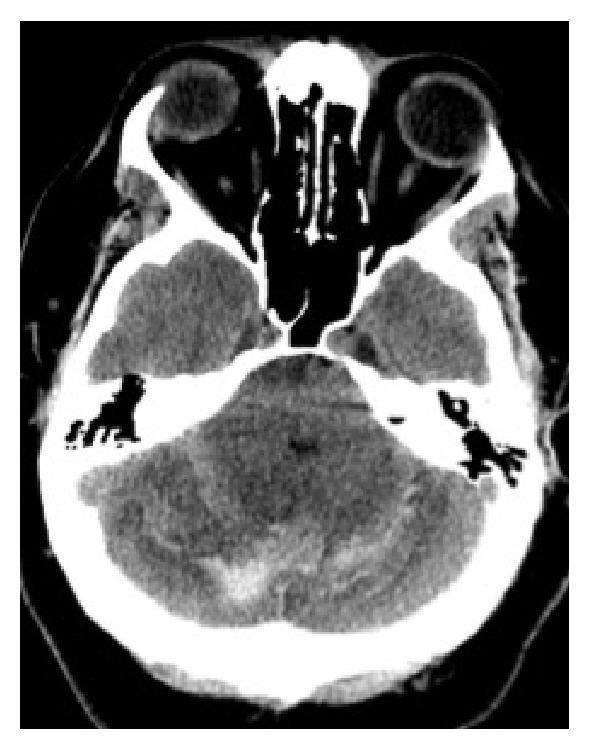

We report the case of a 51-year-old man with no significant past medical history, who underwent elective revision spinal surgery and subsequently developed intracranial hypotension, remote cerebellar haemorrhage (RCH), and mild hydrocephalus on the fourth postoperative day. Remote cerebellar haemorrhage is a known complication of supratentorial surgery. This iatrogenic phenomenon may also occur following spinal surgery, due to dural tearing and rapid cerebral spinal fluid (CSF) leakage, resulting in intracranial hypotension and cerebellar haemorrhage. This complication may result in severe permanent neurologic sequelae; hence, it is of pertinence to diagnose and manage it rapidly in order to optimise patient outcome.

我们报告了一例51岁男性病例,该患者既往无重大病史,接受了择期脊柱翻修手术,术后第四天出现颅内低压、远隔性小脑出血(RCH)和轻度脑积水。远隔性小脑出血是幕上手术的一种已知并发症。这种医源性现象也可能在脊柱手术后发生,原因是硬脑膜撕裂和脑脊液(CSF)快速漏出,导致颅内低压和小脑出血。这种并发症可能导致严重的永久性神经后遗症;因此,快速诊断和处理该并发症对于优化患者预后至关重要。